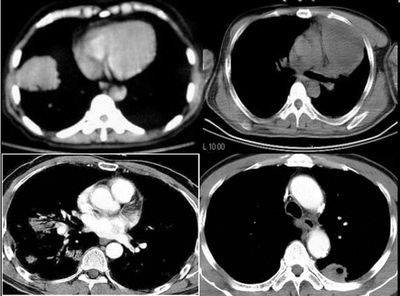

球形肺炎是大叶性肺炎的一种特殊表现[1],以肺的渗出实变为主。它的机理未明,可能是由于抗生素的广泛应用,大叶性或节段性肺炎发展受到限制而形成球形,其形成又与病缘菌的毒性数量及机体的免疫能力有关。病人多有感然症状,某些病人无明显感然症状。病变呈球形或椭圆形,大小不等,病灶密度多均匀,ct值稍低于软组织密度;或中央密度高,边缘密度低,显示晕圈状改变;有时可见空洞[2]。病灶边缘比较规则,也可不规则,有毛刺或呈锯齿状改变,但较模糊。位于肺周区,贴近胸膜,部分病栽表现为两侧缘垂直于胸膜,呈刀切样平直边缘。病灶周围血管纹理增多、增粗、常有局限性胸膜增厚。球形肺炎抗炎两周后,病灶即有缩小,最后能完全吸收。

球形肺炎:病变密度相对较淡,中央密度略高,ct图片上密度较为均匀,增强中央可出现无强化区。病变邻近胸膜反应较为显著,可表现为增厚、粘连(可以比较广泛),病变内可以见到大血管的贯穿,周围及近肺门侧可以见到血管纹理增多、增粗,可有支气管充气征象,两侧可垂直于胸膜或呈方形,边缘可为刀切征,它可以出现毛刺样的类似改变,短期内抗炎治疗有效。